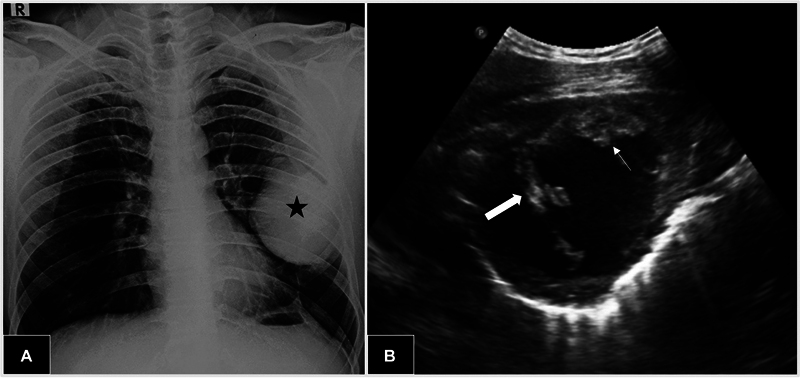

Pulmonary sclerosing pneumocytoma is a rare benign neoplasm typically seen in middle-aged women. The exact preoperative diagnosis is quite challenging considering its nonspecific clinical and radiologic features along with complex histology. Moreover, obtaining an exact histopathological diagnosis can be difficult especially with the small biopsy specimens. Most patients are generally asymptomatic with incidental detection of peripheral, homogenous, solitary pulmonary nodule. It is essential to differentiate it from other mimickers including malignant lesions as limited surgical resection is curative in these cases without adjuvant therapy. We present a rare giant cystic variant of pneumocytoma, in a young male, which was initially mimicking inflammatory myofibroblastic tumor even on preoperative histology.

Abstract Image